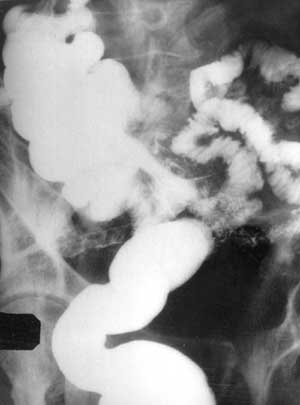

Рис. 5. Одномоментная пре- и постстомальная энтерография при петлевой илеостоме. Постстомальный отдел подвздошной кишки и баугиниева заслонка проходимы для контраста.